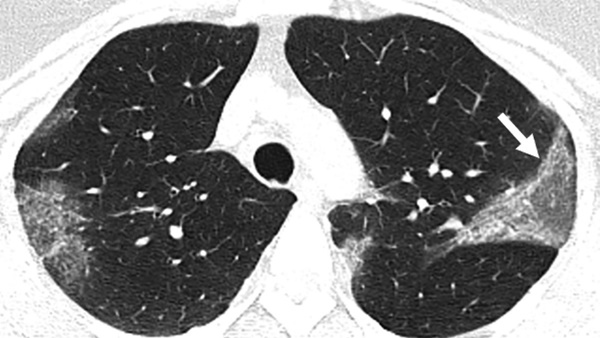

Hình ảnh tổn thương phổi đặc trưng của các bệnh nhân nhiễm Covid-19

Khi mất đi lớp bảo vệ, đường hô hấp sẽ bị chất bẩn, dịch lỏng và virus tràn ngập. Cách thức tấn công này khiến nhiều bệnh nhân Covid-19 bị viêm cả 2 lá phổi.

Khi sang giai đoạn 3, tổn thương phổi nặng sẽ tiếp tục lan rộng dẫn tới suy hô hấp cấp tính (thở nhanh, khó thở, tím tái…). Trong trường hợp bệnh nhân có hồi phục, phổi sẽ bị tổn thương không thể phục hồi.